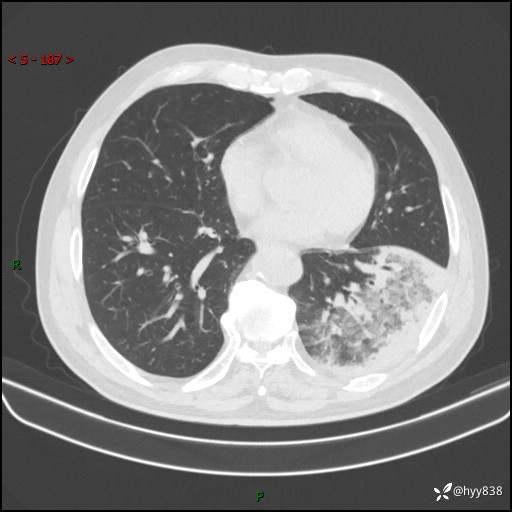

59岁/男,发热伴咳嗽3天。白班偶遇,“大叶性肺炎”,病原体挑战---结果公布~

【患者信息】:59岁/男

【主诉】:发热伴咳嗽3天

【检查】:胸部CT平扫